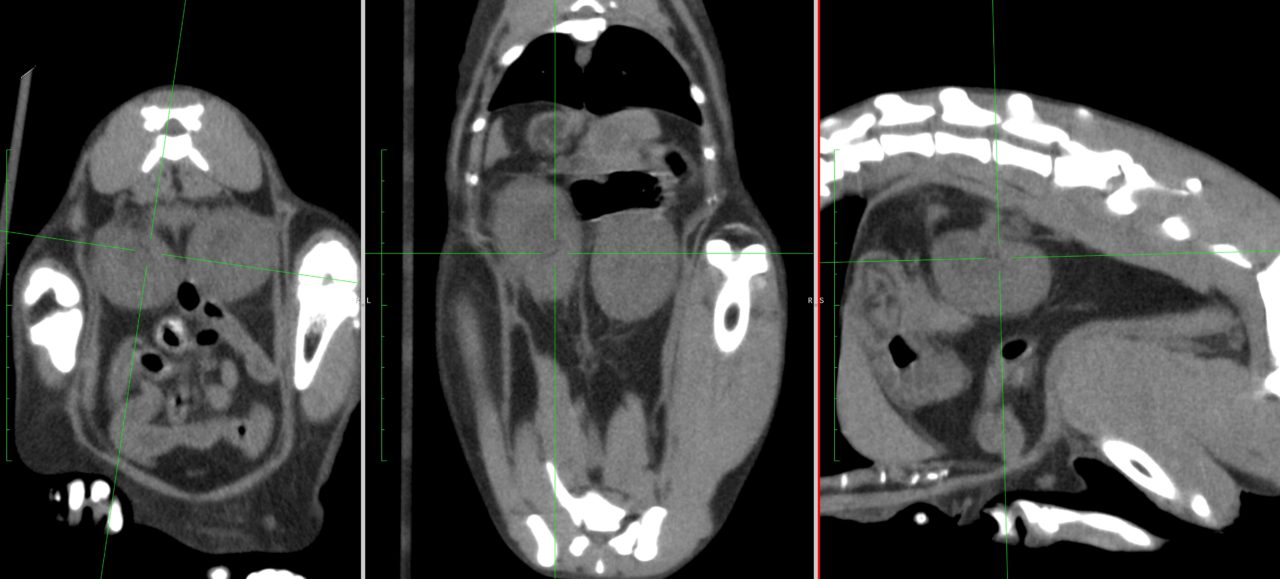

猫さんが急に具合が悪くなって、かかりつけ医を受診したところ血液検査で腎数値が著しく上昇し、高カリウム血症になっているとのこと。すぐに原因を調べて必要な処置をして欲しいとのことで来院されました。無麻酔CTでは尿管結石は確認されませんでした。すぐに拡張した腎盂に腎瘻カテーテルを設置し、尿の排泄路を確保しました。数日後アシドーシス、高カリウム血症は改善されました。尿管炎に伴う尿管の運動機能障害、エックス線に映らない結石の閉塞(99%近くシュウ酸Caなのでまず考えにくい)などが考えられましたが、腎瘻カテーテルを一時的に閉鎖すると腎数値が上昇傾向にあるため、両側の尿管の機能障害と判断しSUBシステム(人工尿管)によるサルベージを行いました。手術の翌日には腎数値は正常に回復しました。CTによる猫の尿管結石の検出感度は非常に高く、術式の決定や治療方針について細かい評価が可能です。今後は血液検査で腎数値のモニタリングを行いながら、定期的にインプラントの洗浄やメンテナンスが必要になります。